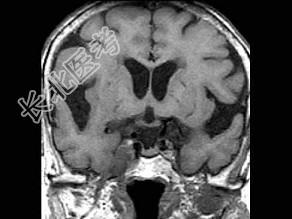

- 单项选择题男,46岁, 面部肌肉麻木、疼痛,咀嚼困难, 牙痛,MRI检查如图, 最可能的诊断是 ( )

B、三叉神经鞘瘤